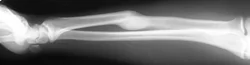

Forearm Fractures

- (Considered as a joint)

- Management:

- Undisplaced:

- Possible conservative - cast & follow up

- Displaced:

- Anatomical Open reduction and internal fixation by Plating and screws( best fixation)

- Early motion - Prevents stiffness